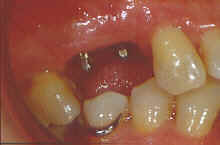

10- IMPLANTE CON FALTA DE HUESO POR VESTIBULAR

20- IMPLANTE CON FALTA DE HUESO POR VESTIBULAR